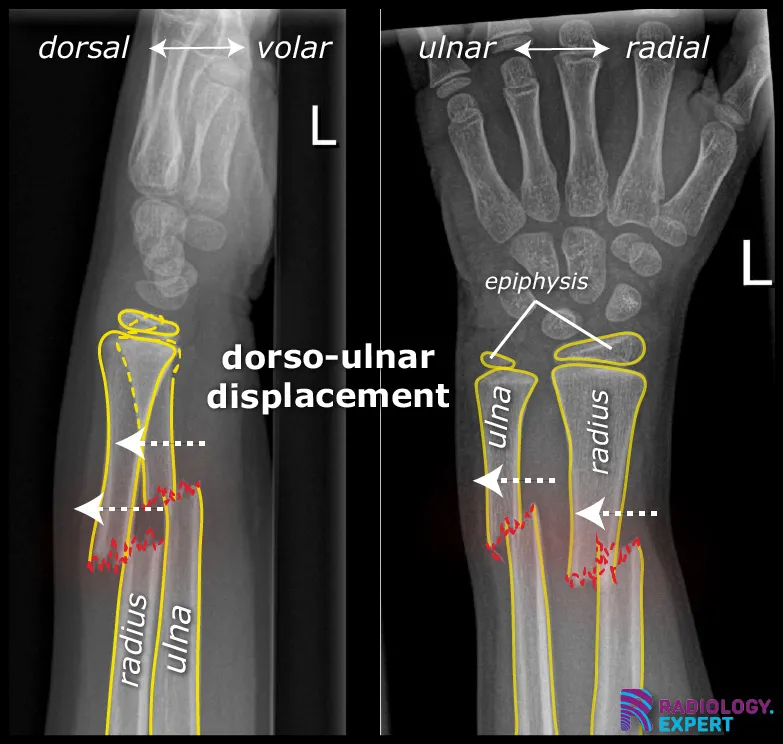

Figure 1. Lateral and anteroposterior view of the left forearm/wrist. A child (9 years old) with a distal radius shaft and ulna shaft fracture. Both show dorso-ulnar displacement of approximately one shaft width.

Click image to see overlay